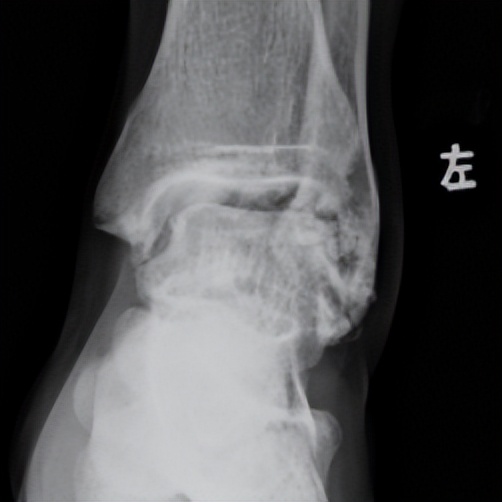

林先生来到省二医后,何河北医生为其进行了详细查体,检查后确诊为踝关节不稳+滑膜软骨瘤。

何河北制定了详细的手术方案,为患者开展踝关节镜下滑膜软骨瘤取出术+距腓前韧带重建术。他从患者踝关节中取出32颗“珍珠”(关节游离体),然后进行踝关节外侧韧带重建。

▲术前可见踝关节前方有大量“珍珠”。